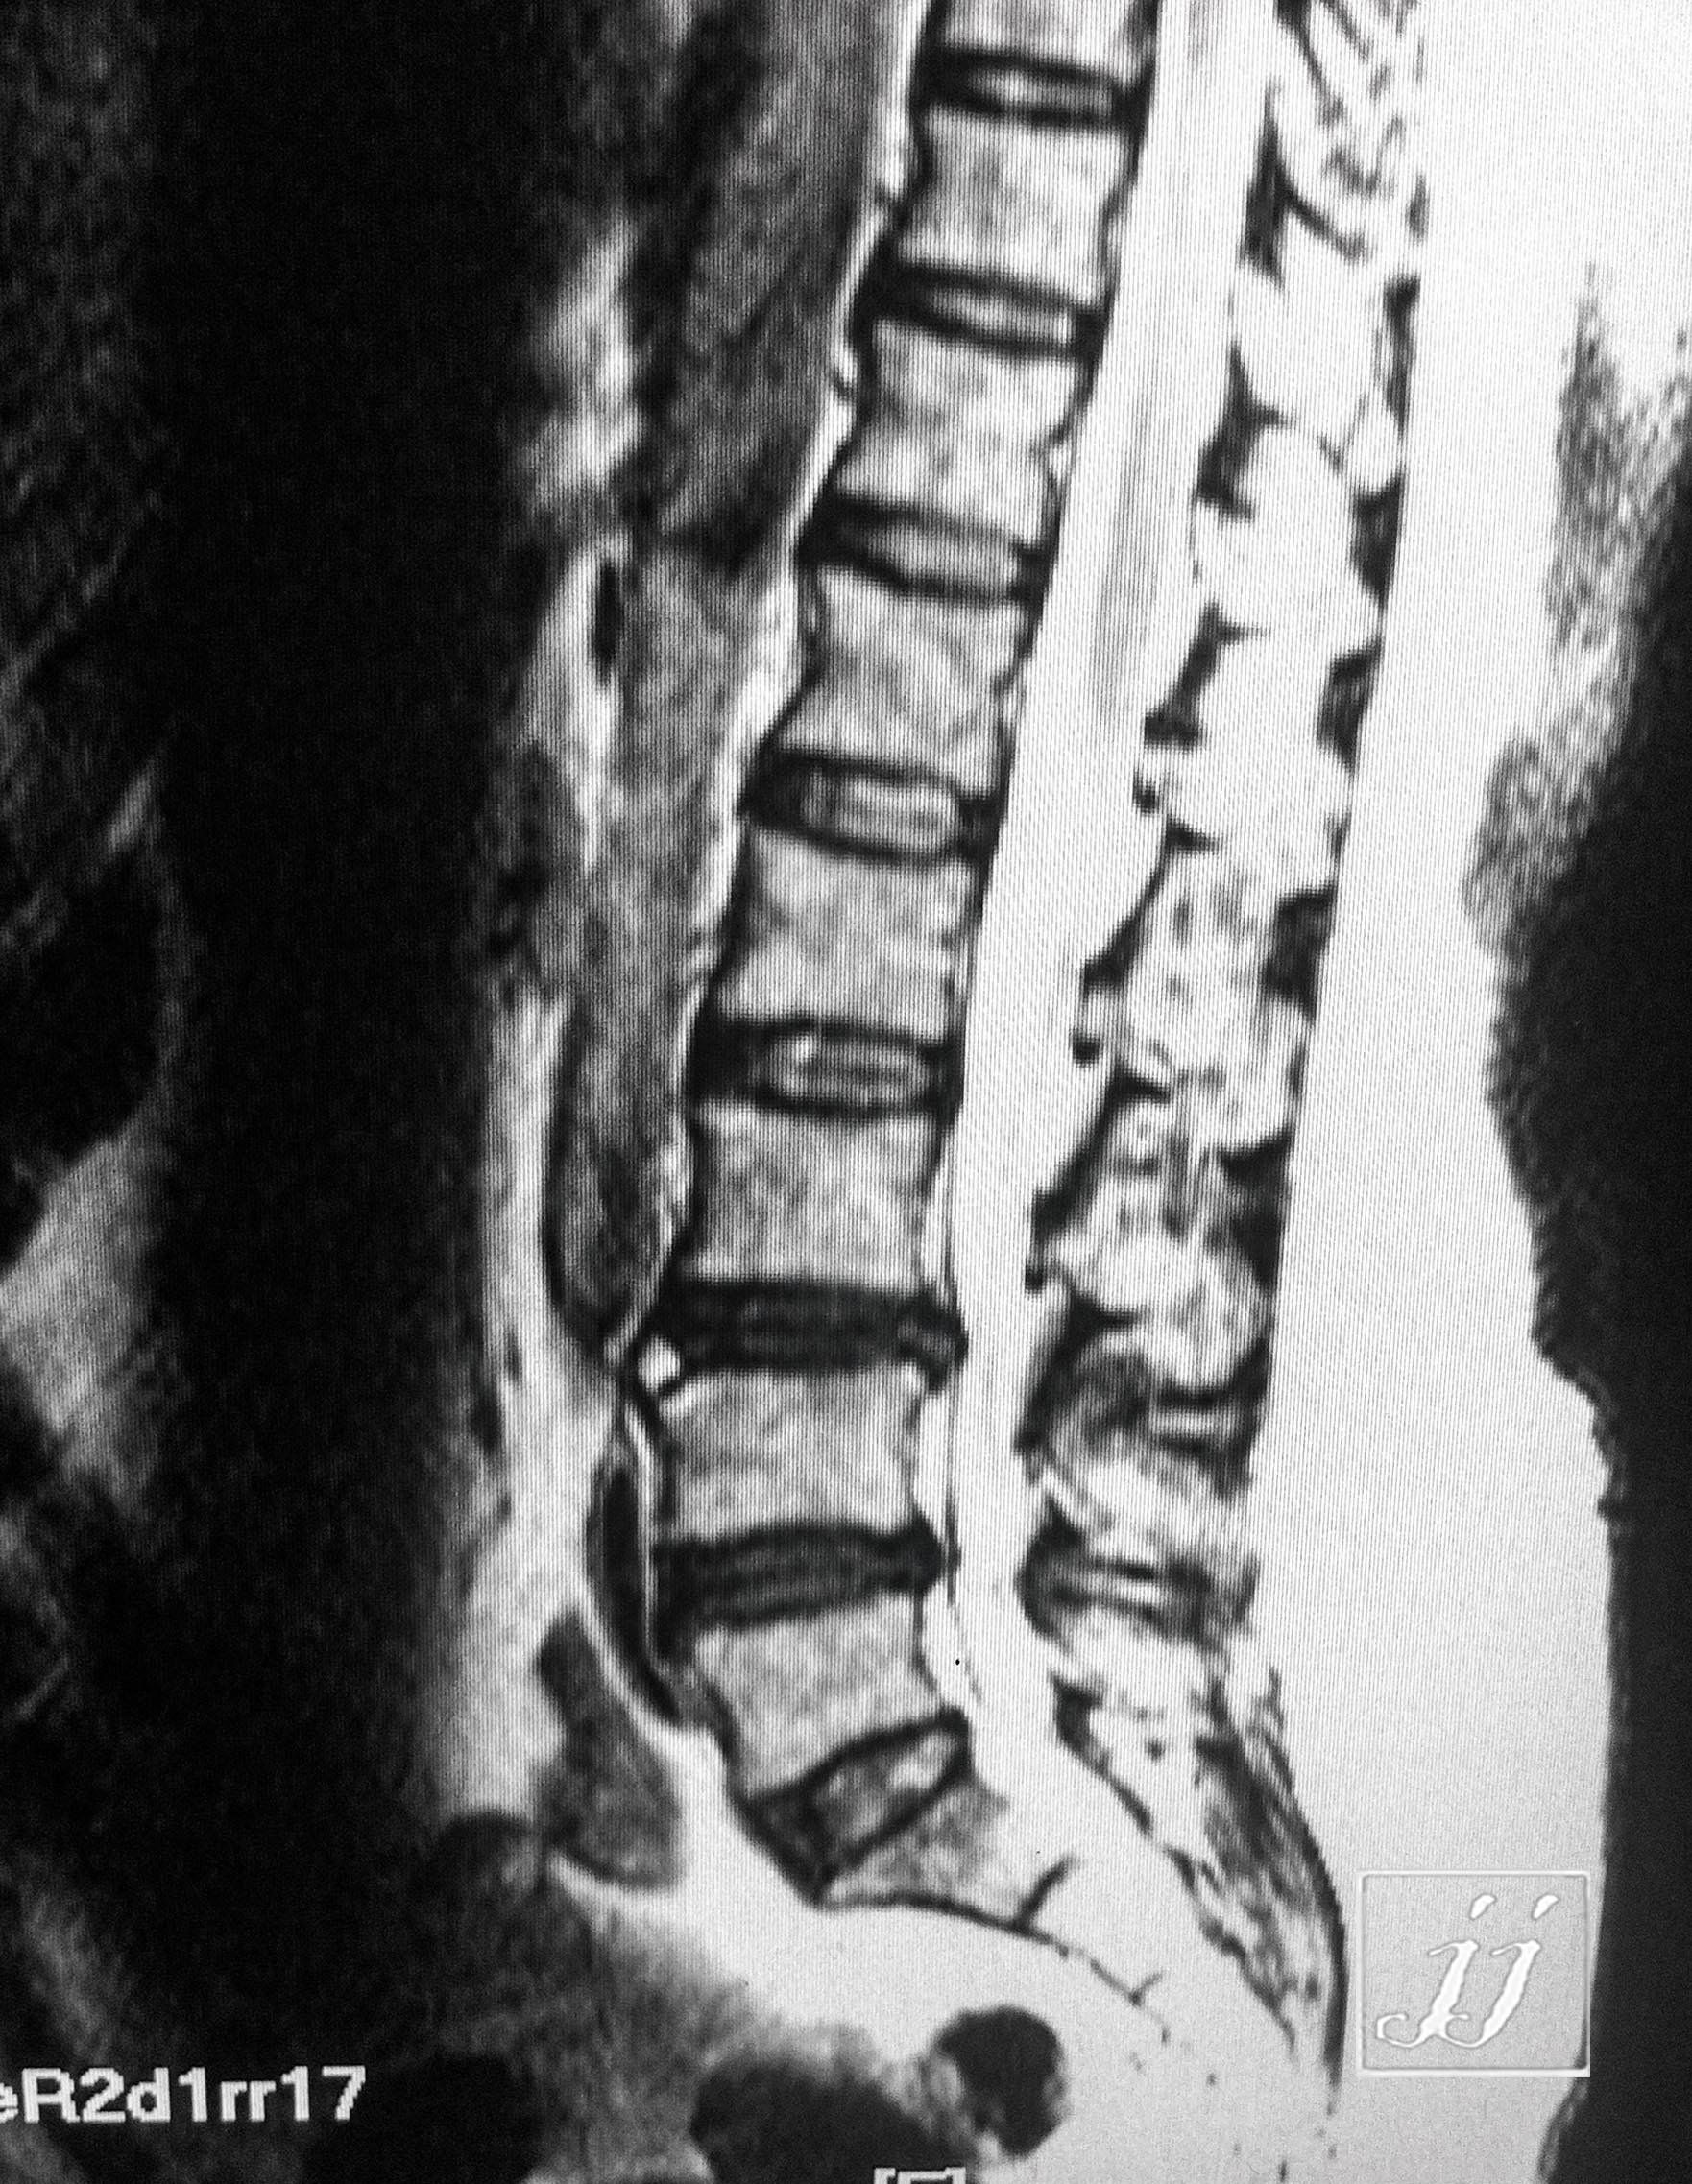

Spine- L4 limbus vertebra (2)